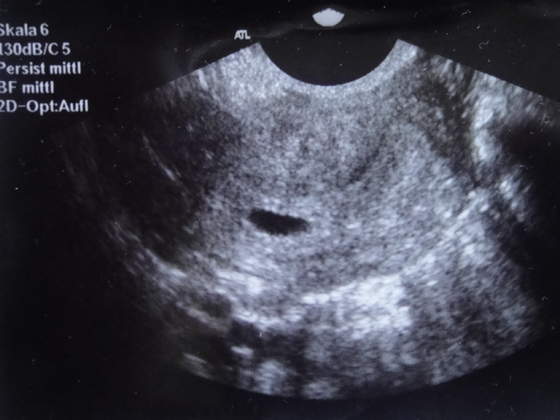

o znalazlam cos podobnego, tzn moj pecherzyk jest mniejszy ale cos podobnego w nim siedzi, tu zaznaczyl ktos ze to dziecko, no ja mam nadzieje ze u mnie tez